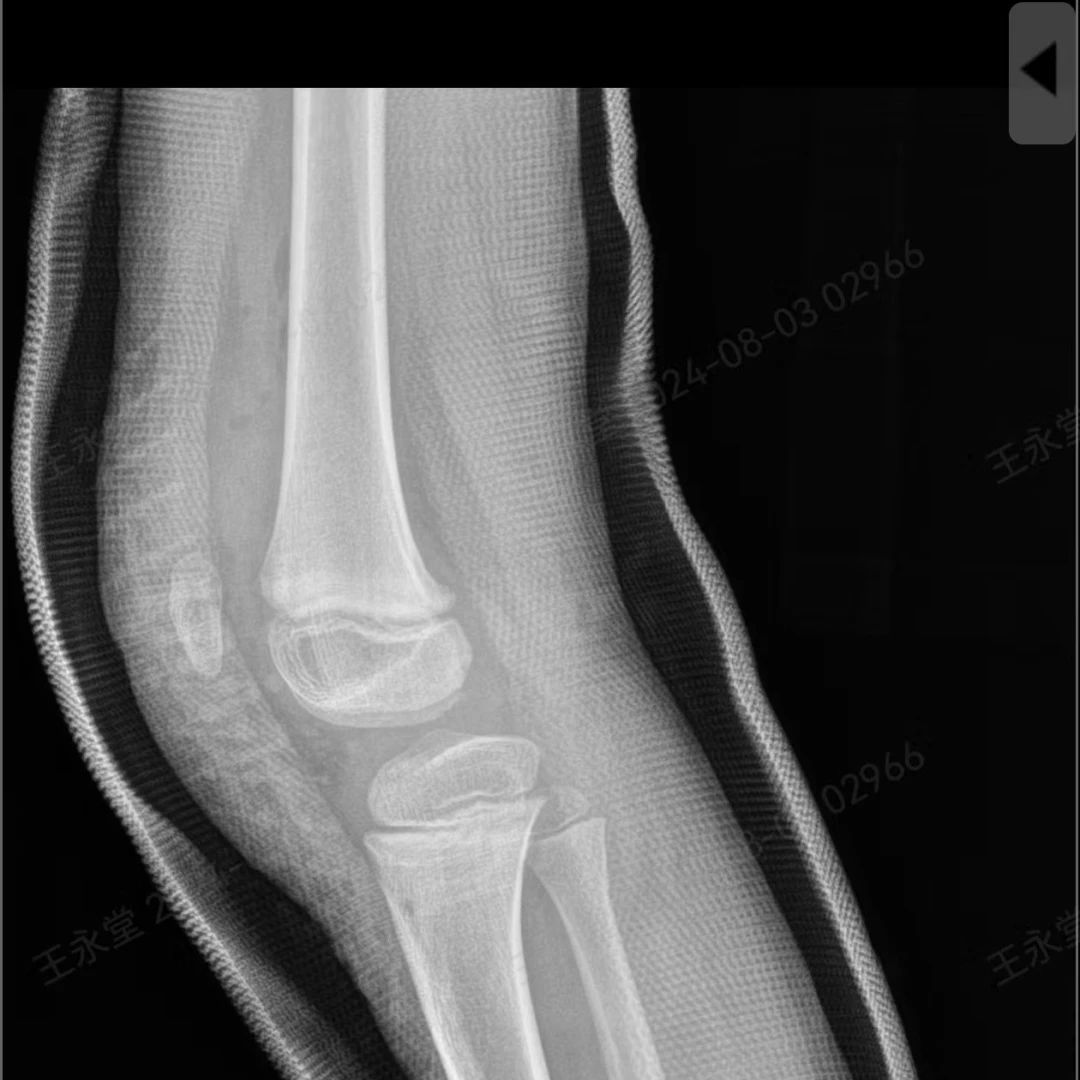

看着孩子开心,爸妈也愿意花钱,但是这项“飞起来”的娱乐项目,背后却暗藏危险。一天,妈妈带5岁的可乐来到了游乐场,想着趁开学前让他好好玩一回。进了蹦床馆,可乐兴奋不已,起跳、弹起、落下……玩得不亦乐乎。可乐用尽全身力气向上蹦,希望能跳得高一点,谁知,落下的时候没把握好平衡……狠狠摔下后双膝着地!他疼得哇哇大哭。妈妈跑去一看,可乐膝盖又红又肿,不能动弹。立刻带他到医院就诊,X线显示膝关节没有骨折,妈妈认为有惊无险,休息几天就好了。

随着可乐一天天长大,妈妈发现他的膝盖和别的孩子不一样,双侧髌骨(俗称:膝盖骨)逐渐向外侧偏斜,勉强能正常走路,但是屈伸膝关节时,膝盖的畸形越来越重,尤其是在跑步运动时,总感觉腿不听使唤,剧烈运动时膝盖就疼,而且特别容易摔跤,久而久之,原本活泼的可乐,也不愿出去运动了。

闫桂森主任细查体,发现可乐的双侧膝关节发育畸形,髌骨滑车发育不良,建议尽快手术治疗,让髌骨重回正常位置,促进关节生长发育,如果再拖,膝关节发育进一步畸形,将会影响关节功能!

术后治疗效果良好,可乐的髌骨重回到了正常的位置……